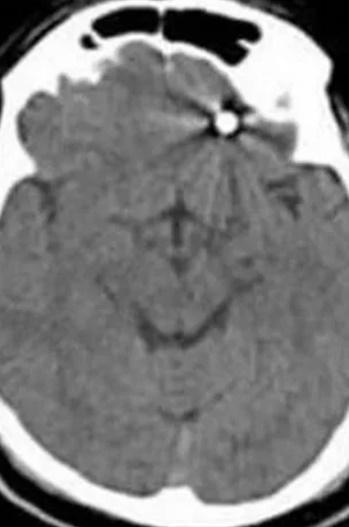

牙醫立刻將Ramazan Yılmaz送去當地一間醫院,但隨即離開,醫護人員馬上幫他進行斷層掃描,發現螺絲釘竟然進入Ramazan Yılmaz眼睛後方的大腦以及脊髓液所在的區域,需要立即進行手術。但手術前醫生亦警告Ramazan Yılmaz,他可能因此失去生命,他便趁機跟子女和好。歷經數小時的手術,醫生從他的大腦取出那口螺絲,至今已經康復出院。事後,Ramazan Yılmaz要求為他植牙的牙醫退還植牙費及賠償醫療費,牙醫則指,事件是「醫療併發症」所導致,表明不會退款和賠償,Ramazan Yılmaz無法接受,決定對牙醫提出訴訟。